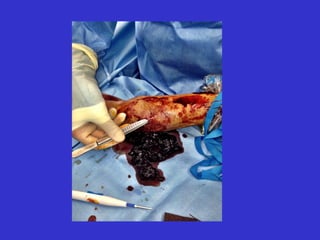

Intraluminal Thrombus

Intraluminal

thrombus

“Saran-wrap” layer of thin fibrin and thrombus

Tunneled hemodialysis catheter

that had been used for 6 weeks